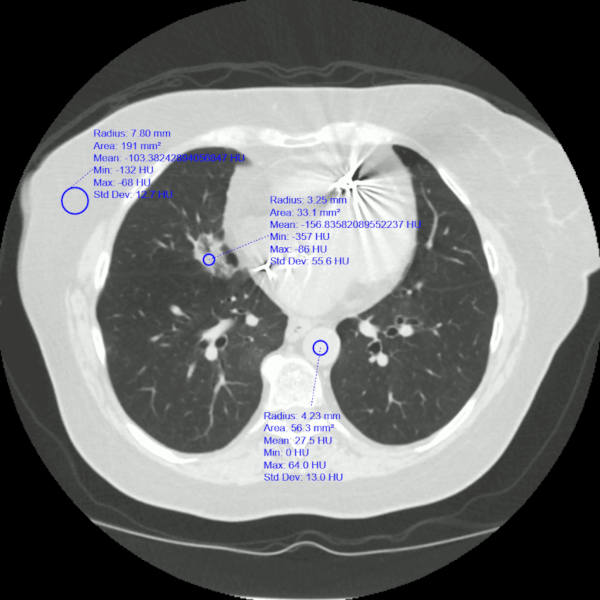

Acute aspiration

Lipoid pneumonia. A 77-year-old woman with dysphagia and achalasia following a stroke presented with recurrent lung infiltrates, including a persisting right middle lobe lesion. Hounsfield units (HU) measurement was -157, consistent with lipoid pneumonia. Comparative subcutaneous fat and aorta (blood/tissue) HU are shown

From the collection of Dr Augustine Lee, used with permission of Mayo Foundation for Medical Education and Research, all rights reserved